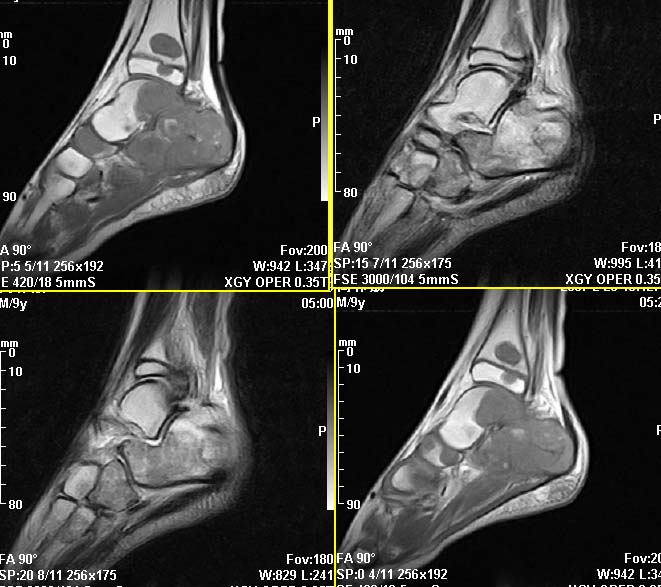

m,9y,左足肿痛半年,无皮肤发红,诱因为外伤后起因。无发烧,无其他疾病。临床考虑多发血管瘤。mri增强后有强化,请分析。是骨髓瘤吗?

左足多发囊状膨胀性骨质破坏,边较清,关节间隙及软组织未见明显异常。结合临床。可排除炎症性病变。病变中心为骨髓腔。有强化。中心坏死。嗜酸性肉芽肿可能大。

多发内生性软骨瘤

结合临床考虑血管瘤侵犯左足骨质。

今天从天津肿瘤医院传来消息:病理结果是非骨化性纤维瘤。